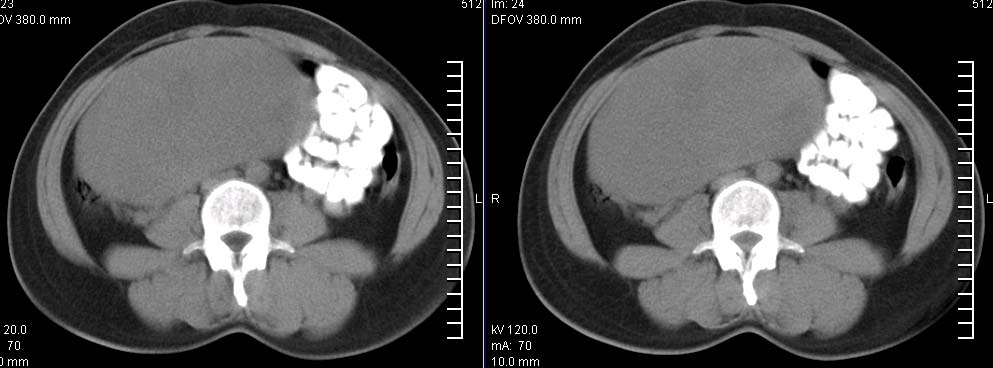

标题: CT9722:卵巢巨大占位,约10*18*21CM大小

卵巢巨大占位,约10*18*21cm大小

卵巢囊腺瘤可能性大.可见低密度

考虑:右侧卵巢囊性瘤可能性大 建议增强扫描。

肿瘤的密度有点高.和子宫差不多?且和子宫相连呢?我考虑来源于子宫,子宫巨大子宫肌瘤可能性大!(局部有坏死?)

囊腺瘤不管是浆液性,还是黏液性的,液体成分应该占的比例很大吧!!这个病灶其实是个实性肿块,更看不到囊腺瘤所能见到的分隔??请笔者提供ct值?望大家再仔细分析??

右侧卵巢的巨大占位,病灶大部分呈实性,以恶性可能大。

右侧附件区巨大囊性肿块,边缘光滑,密度较高,左侧缘由多个低密度区,首先考虑囊腺瘤可能。